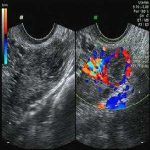

请问:得了子宫肌瘤是否可以怀孕?如果我到北京安太医院治疗,是否会影响我怀孕,子宫肌瘤不大,一分钱硬币那么大,着急怀孕。

北京安太医院答复:有子宫肌瘤不建议怀孕,子宫肌瘤怀孕危险多多,怀孕后子宫肌瘤生长迅速还易变性,影响胎儿的生长发育,建议取掉肌瘤后再怀孕,子宫肌瘤不大,北京安太医院通过三D腔镜下取出,两三个月怀孕没有问题,不会影响以后怀孕,治疗有保障!可签约!

再者,也有些人未进行孕前的检查,怀孕后发现子宫肌瘤,怀孕早期发现肌瘤仍然可以腔镜切除,带瘤怀孕凶多吉少。